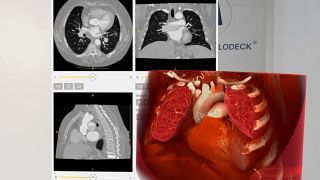

Low-dose CT, high-impact: VR is redefining pediatric surgery Publication

Low-dose CT, high-impact: VR is redefining pediatric surgery

Early detection and timely surgery are key for healthy lung development in babies. Low-dose CT scans reduce radiation but make images harder to interpret. Researchers at the University of Bonn created patient-specific 3D digital twins viewable in VR, improving visualization, spatial understanding, and collaborative decisions for the smallest patients.